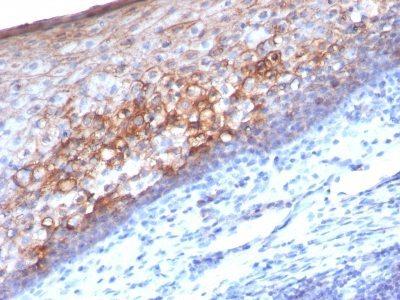

Positive Control

A-375, HUV-EC or HeLa Cells. Tonsil or Melanoma.

Tumor expression

Melanoma

Antibody application notes

Higher concentration may be required for direct detection using primary antibody conjugates than for indirect detection with secondary antibody|Immunohistology (formalin)|Staining of formalin-fixed tissues requires boiling tissue sections in 10 mM Tris with 1 mM EDTA, pH 9.0, for 10-20 min followed by cooling at RT for 20 minutes|Flow Cytometry 0.5-1 ug/million cells/0.1 mL|Immunofluorescence 0.5-1.0 ug/mL|Optimal dilution for a specific application should be determined by user